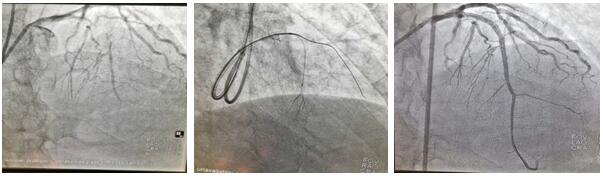

患者劉某某, 68歲男性,1月前于我院診斷:急性非ST段抬高型心肌梗死。行冠脈造影提示前降支近段100%閉塞,同側穿膈支側枝循環形成,回旋支近中段狹窄80%-90%,LAD為CTO病變,擬行完全血運重建治療,順利于回旋支病變處植入1枚支架,術中反復嘗試各種導絲均未能開通LAD血管,歷時近3小時,只能放棄,擇期再處理。面對困難,面對失敗,心血管二病區左梅主任醫師團隊,反復閱片,尋找失敗原因,知難而上,勇于挑戰,制訂新的手術策略,決定為患者第二次開通LAD閉塞病變。在經過充分的術前討論后于2020年7月2日第二次上臺,由于患者LAD近段CTO病變,前次正向途徑介入失敗,右冠無良好側枝形成,無逆向條件,擬行乒乓技術同側微導管造影顯示閉塞遠段,提供正向導絲的指引,進入遠端血管真腔;若失敗,微導管跟進至血管內膜下,采用ADR(正向內膜下重回真腔)技術完成手術。手術的重要點在于控制血腫的大小。術中采用同側雙指引導管至左冠脈開口(乒乓技術),在一側指引導管送微導管至穿膈支中段,超選擇造影清晰顯示LAD-CTO遠段,另一側指引導管內反復調試FieldXT-A導絲順利通過閉塞病變至遠段,在助手及導管室工作人員的全力配合下,歷時不到1小時,成功完成手術。術中患者無任何不適及并發癥發生,一家人很是欣喜。